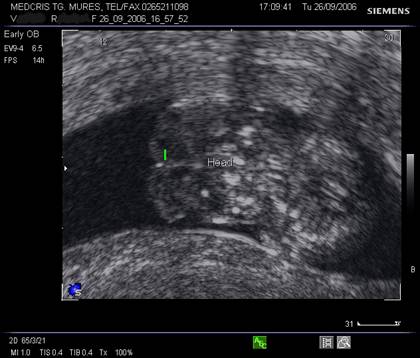

Fig. nr.108. Sarcina 7 saptamani la ecografia abdominala.